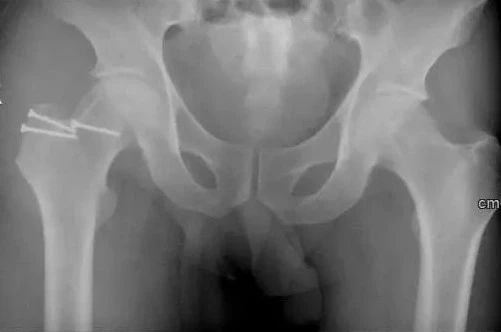

术后X光片

为减轻患者疼痛,改善髋关节功能,延缓股骨头坏死进展,在麻醉科、手术室团队的通力合作下,骨科张华,范志勇和关节亚专业团队张宏亮、张秉时、靳赢超为患者成功实施右股骨头坏死外科脱位+取髂骨植骨术。

张华介绍,对中晚期患者,该术式能够完全清理股骨头的坏死组织,重建股骨头的强度,缓解疼痛、改善关节功能,延缓或避免青壮年患者过早行全髋关节置换术。该手术具有疗效优良,安全性高,并发症少,医疗费用低等优点。